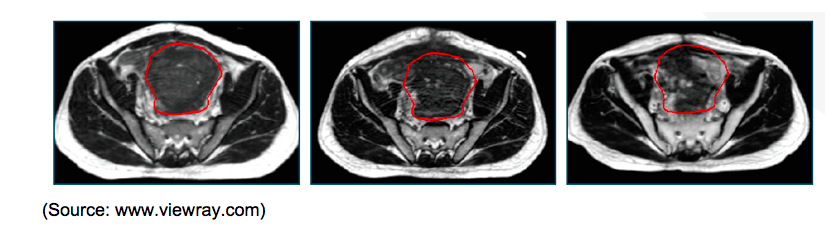

Clinical Studies: Instead of relying on existing bones or implanted fiducial markers, the MRIdian system’s real-time imaging enables the physician to track the movement of the tumor and the surrounding healthy tissue directly. With better soft tissue imaging provide by MRI, the patient can be aligned more accurately for treatment. When the tissues have changed and the treatment plan is no longer acceptable, on-table ART allows for the reshaping of the dose to maximize target coverage and healthy tissue sparing without moving the patient. During beam delivery, the treatment beam automatically pauses in situations where a tumor is in close proximity to a critical organ, such as the heart during lung and breast cancer treatments or the rectum during prostate cancer treatments. The real-time tracking of tissues has enabled physicians to treat patients who would not have been considered for radiation therapy.

Sigmoid Colon Cancer with Bladder Invasion; A large sigmoid tumor that was invading the bladder could be located and accurately tracked despite its motion using the MRIdian system.

The ability of MRIdian to simultaneously image while treating not only enables clinicians to treat cancers that would be difficult to treat using other radiotherapy systems, it also enables the clinicians to hit the tumor “hard”, with largers doses in less sessions. Using CBCT guided radiotherapy systems, doses of radiation are often fractionated and standard radiation therapy is often given once a day (five times a week) for up to eight weeks. The ability to view the tumor during treatment and the enhanced ability to avoid nearby healthy tissues, potentially allows clinicians to give more intense doses in a single or a few sessions and reduce the significantly reduce the duration of treatment. The reduced duration of treatment is going to be embraced enthusiastically by both patients and healthcare systems.